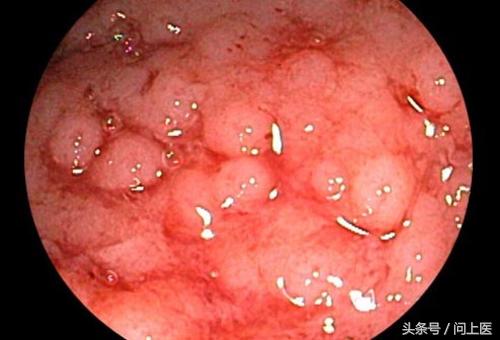

8 / 24 溃疡性结肠炎的诊断

溃疡性结肠炎最准确的检查方法是结肠镜检查,在该检查中,医生会将一个小型相机插入患者的直肠内,以近距离地观察结肠内部,可以观察到该部位是否有溃疡或炎症。医生也会通过该检查来排除克罗恩病、憩室炎和癌症。